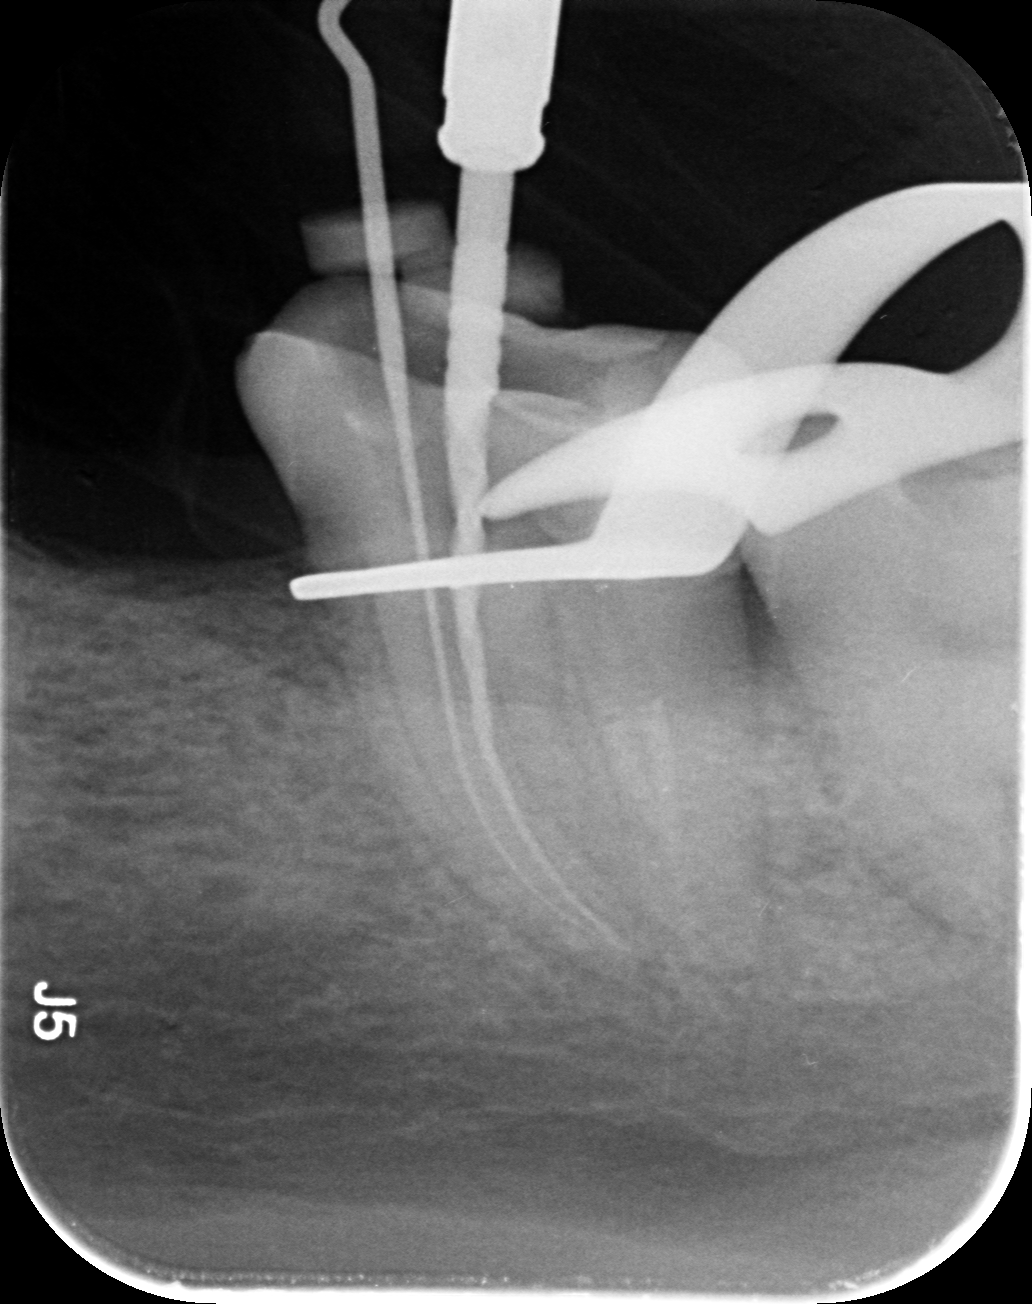

Dantų kanalų gydymas